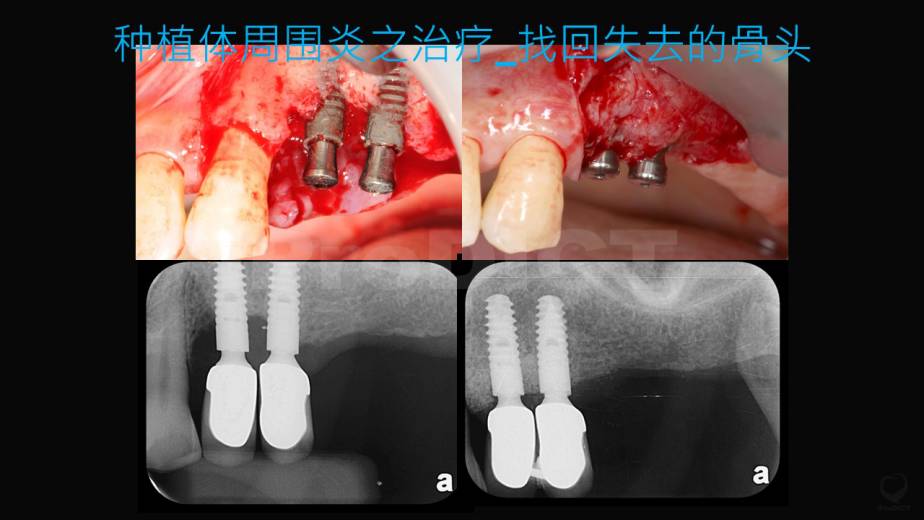

BIC_种植体周围炎之治疗